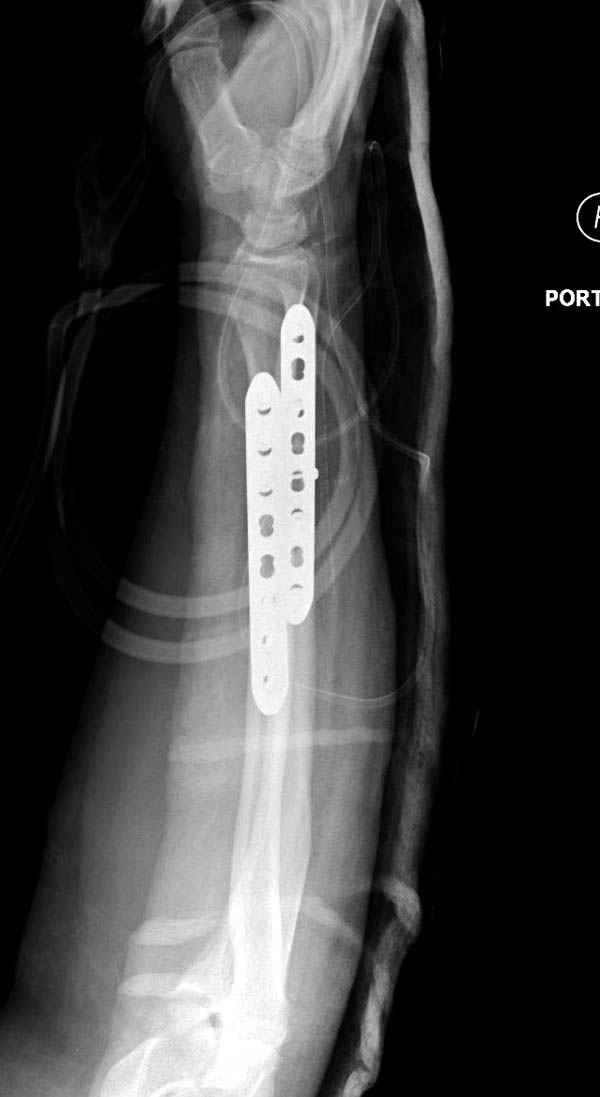

Второй случай, для лечения перелома проксимального

плеча применили пластину "Hand Innovation"

http://www.handinnovations.com/pdf/S3_technique.pdf

Пластина имеет преимущества перед другими "Locking

Implants", потому что пластину можно уложить намного ниже чем другие

пластины и имеется возможности проведения шурупов под 130 градусным

углом, таким образом можно уменьшить операционный разрез в проксимальной

части.

Кроме перелома плеча у больного старый дистракционный перелом T12-L1

оперированный когда-то и кем-то, открытый перелом костей предплечья,

который был прооперирован в ночь поступления, после I&D (хирургической

обработки). Из-за разрыва селезенки при поступлении травма хирургами

произведено удаление.

Имя     : 2 proximal hum +forearm.jpg

Тип     : image/jpeg

Размер  : 32705 байтов

Описание: отсутствует

Url     : http://weborto.net:8080/pipermail/ortho/attachments/20071129/c86944d4/attachment-0007.jpg

Имя     : 3 proximal hum +forearm.jpg

Размер  : 41814 байтов

Url     : http://weborto.net:8080/pipermail/ortho/attachments/20071129/c86944d4/attachment-0008.jpg